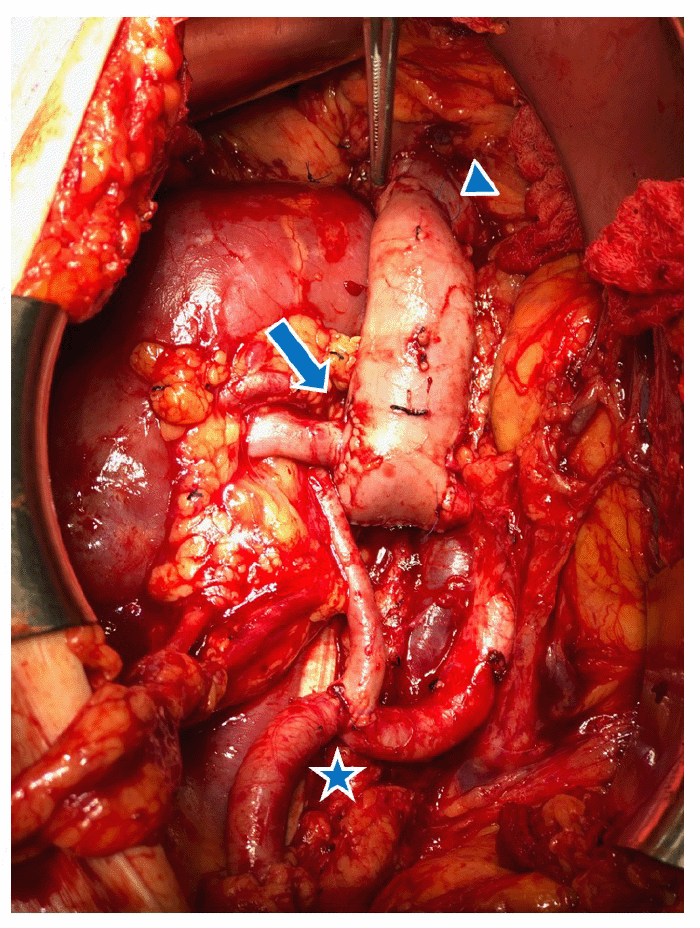

The right-sided deceased donor kidney was then inspected. The donor renal vein had been procured along with 2 cm proximal and 8 cm distal donor IVC. The patient was taken to the operating room for a planned renal transplant in the right iliac fossa, using recipient IVC just proximal to his obstruction as the site for venous drainage of the allograft. An inverted donor IVC conduit was created to maximize the proximity of the allograft to the right iliac artery and bladder. The donor renal vein was divided from the donor IVC, which was then rotated 180º. The donor renal vein was re-implanted at its original orifice, now at the inferior aspect of the IVC, creating a conduit from the renal hilum running superiorly. The inferior IVC cuff was then oversewn. A right lower quadrant curvilinear incision and a right retroperitoneal dissection were performed (Figure 2).

Figure 2. Intraoperative Photo. Published with Permission

Retroperitoneal exposure of the infrarenal IVC obstruction (circled) and common iliac vein (CIV)